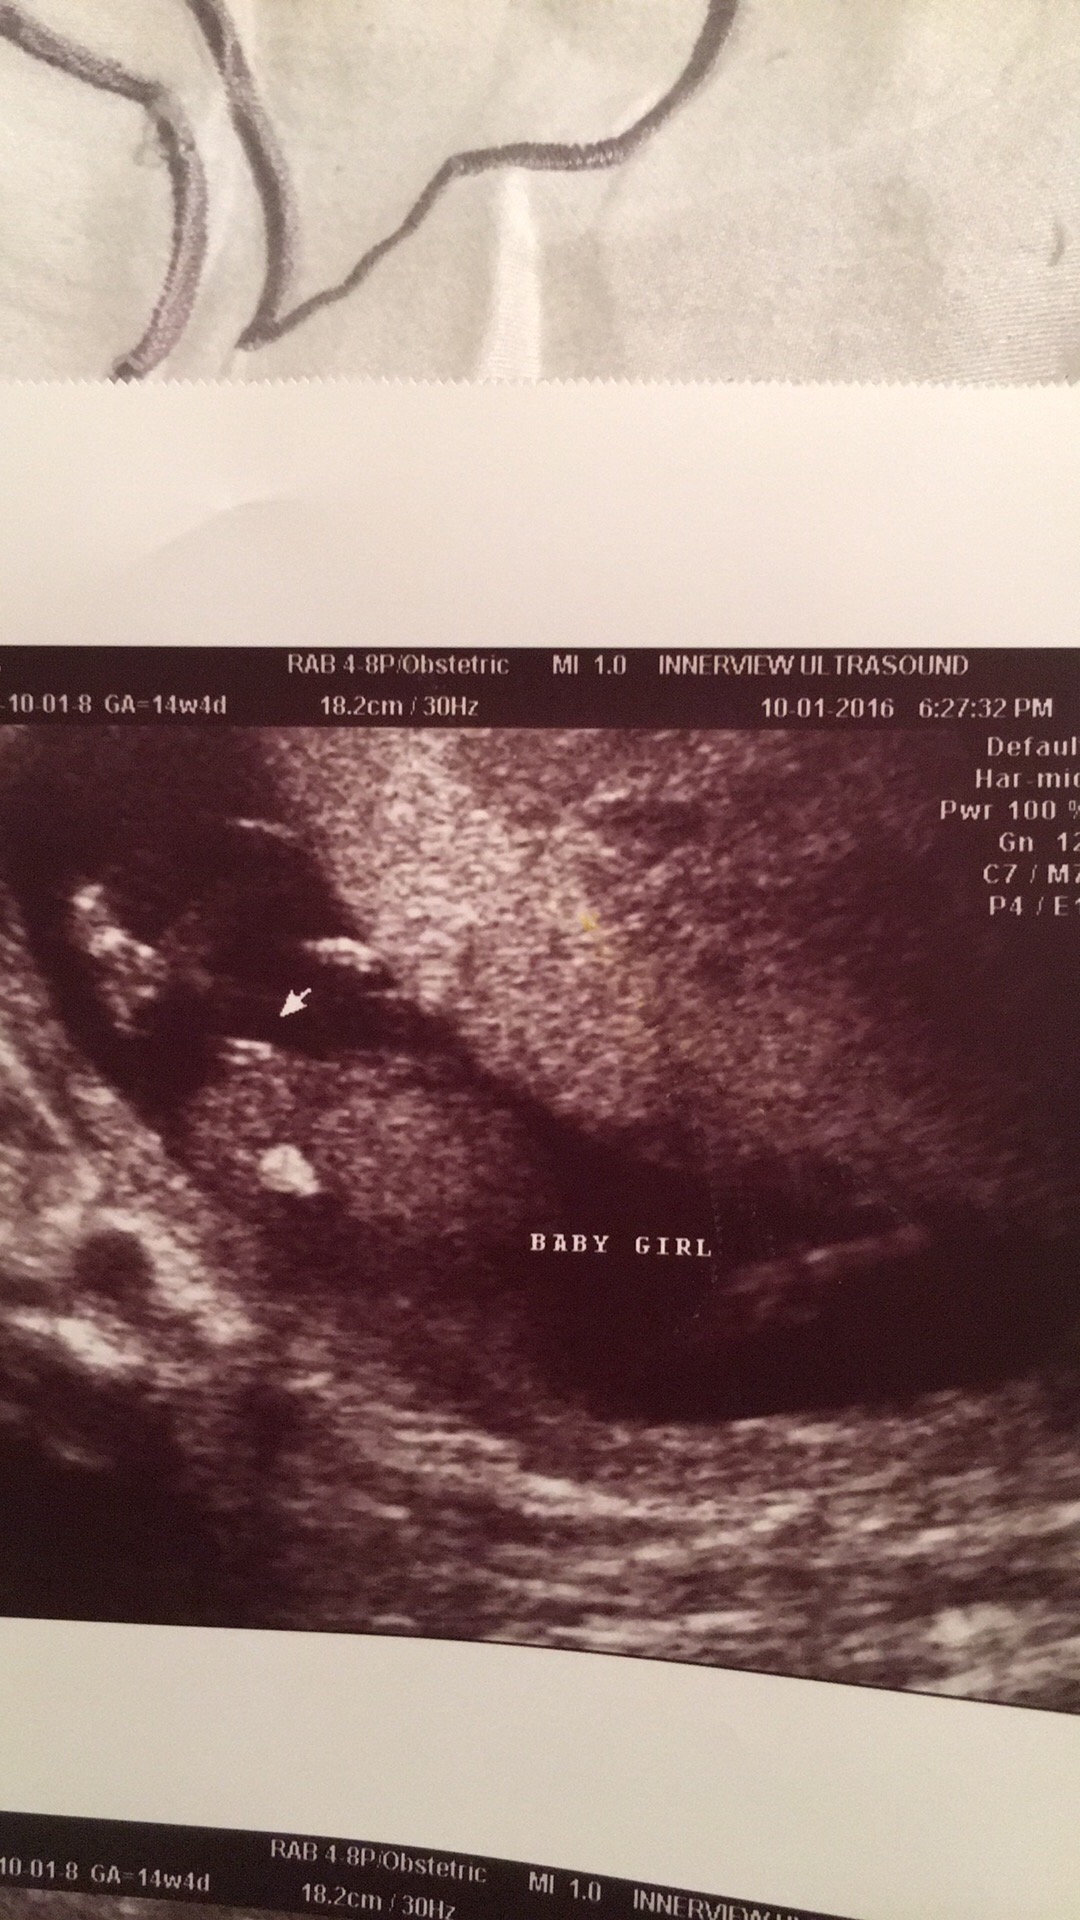

Hi ! I'm currently 17weeks pregnant. I had an early gender scan at 14wks4d. We have 3 boys so when we were told girl we were amazed and so happy !! Can I please take a look and confirm ???? Attachment 33423

Second picture looks very girly too me.

Yes, looks girly

GIRL

looks girly. Congrats!